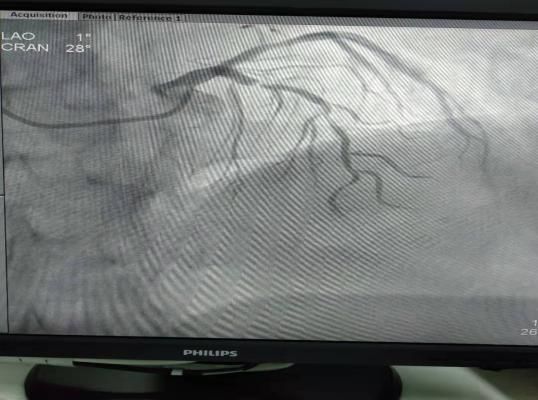

(2)2018年11月2日开展第一例冠状动脉造影术。

患者:孙某  女性48岁 超化镇

图片

术前

术后